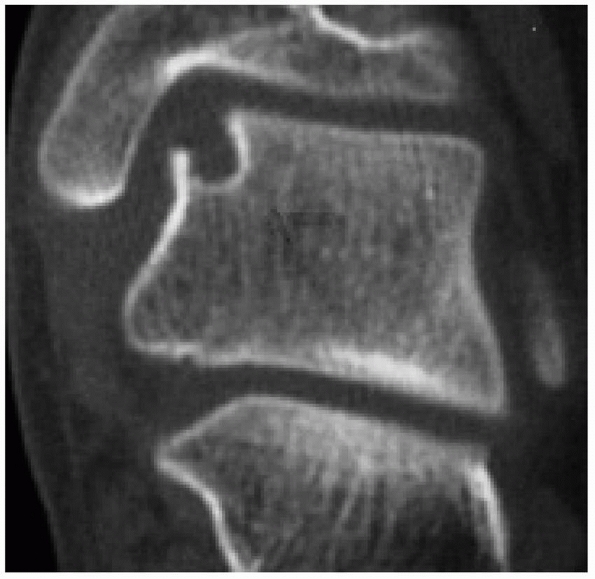

FIGURE 27-12

This CT scan clearly shows a well circumscribed cyst at the base of a stage II osteochondral lesion. This would be classified by Anderson et al.8 as a stage IIa lesion. |